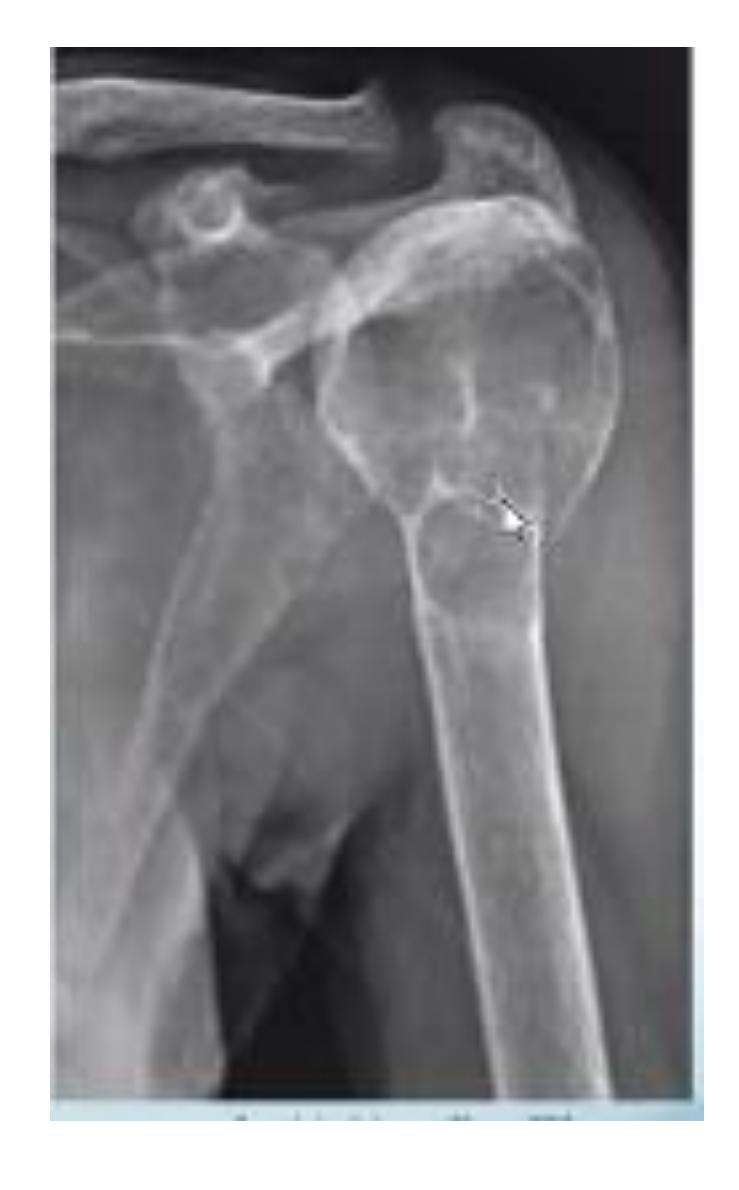

Osteochondroma

What is the diagnosis?

- X-ray showing bony tumor growing away from the epiphysis

- Diagnosis: Osteochondroma

Clinical Features:

- Pain since 2 years in proximal humerus

- Malignant transformation is rare (<1%)

- Treatment: Monitor with ESR, follow-up every 6 months-1 year

- Surgery considered if severe pain (suggesting malignant transformation)

- Surgical risk: Drop hand due to radial nerve injury